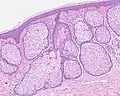

H&E staining of biopsied lesion of sebaceous hyperplasia: Note the multiple, mature sebaceous lobules attached to the central dilated duct in the upper dermis. -